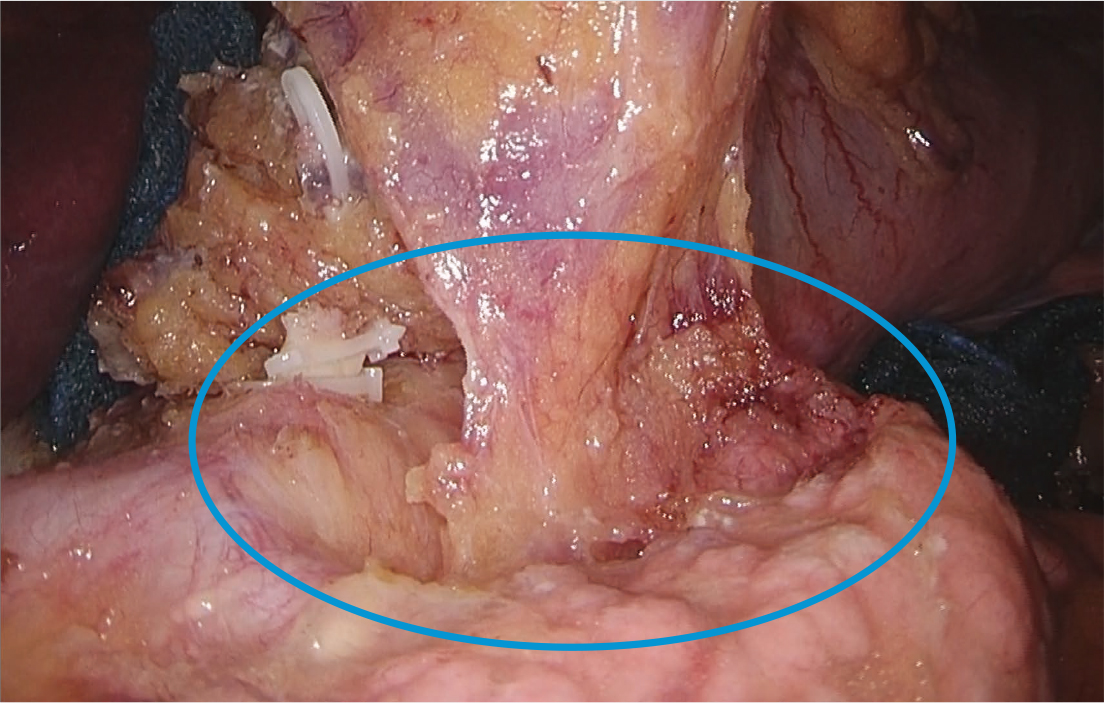

フレキシブルスコープの特徴は、1本のスコープで自由な角度からの視野を得られることであり、それにより対象を常にモニター画面の中心で捉えることができる。さらには最大80度の「見下ろし」により、同じ術野展開では硬性鏡で視認できないような奥深い視野も得ることができる(1)。スコピストは、術者と助手鉗子の位置を把握することで、常に干渉しない位置にスコープを置くことができ、それぞれのストレス軽減のみならず周辺臓器の副損傷予防にもつながると考えられる。

1:硬性鏡とフレキシブルスコープの視野比較

• No.11pリンパ節郭清(硬性鏡)

• No.11pリンパ節郭清(フレキシブルスコープ)